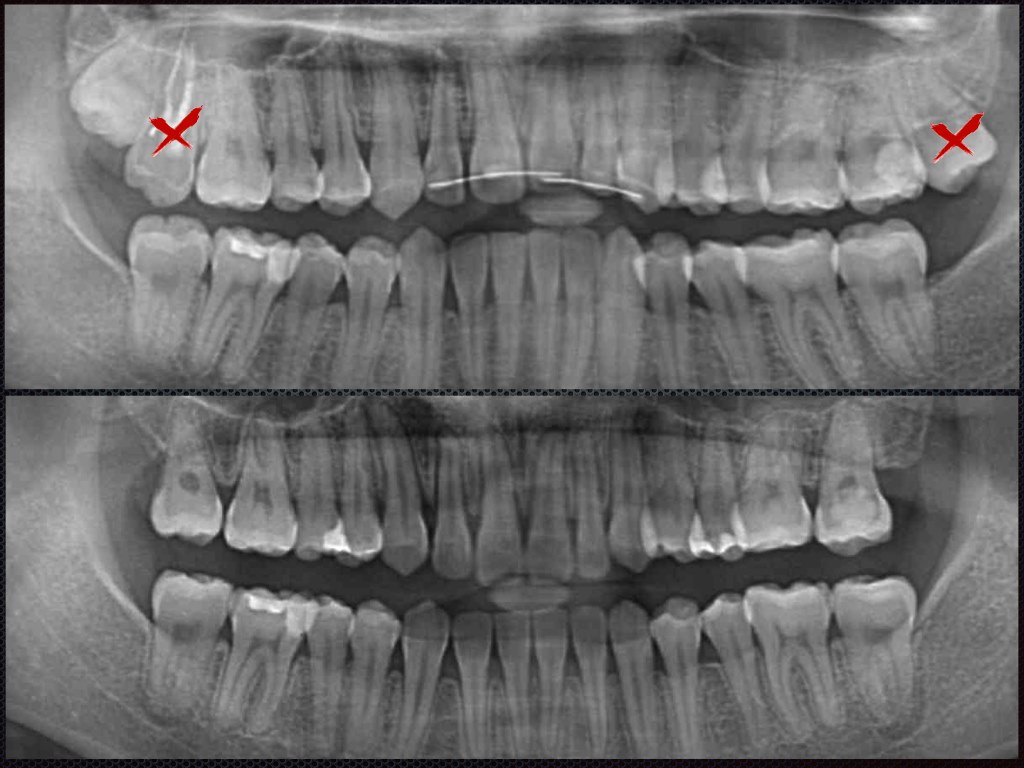

該病患已經做過一次矯正,但覺得矯正完笑起來還是不好看,歪歪的,周醫師評估過發現原因主要是上顎門牙露出太少,而且中線歪斜,最大的主因是病患為骨性戽斗型咬合(即下顎骨較上顎前凸),為了把咬合改正,如果醫師只把上顎牙齒往外移,就會造成微笑曲線失去,做起來也不好看!

為了達成這個目標,需要下顎再打兩隻骨釘後拉,那上顎因為第二大臼齒蛀壞,我們拔掉壞的,拉智齒來取代該牙,左上也打一支骨釘來改善中線。